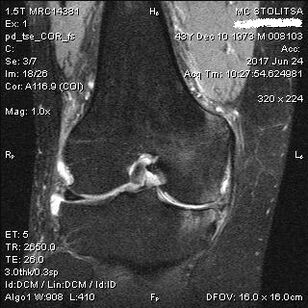

The diagnosis of osteoarthritis of the knee joint is made in the office of a rheumatologist or orthopedist.The doctor examines the affected joint, feels it, listens to complaints and asks additional questions.Performs several tests - for example, asking the patient to bend their leg or take a few steps.If it is then necessary to clarify the stage of the disease or the nature of the pathological changes, he will refer you for further examinations.For example for computer tomography or radiography.